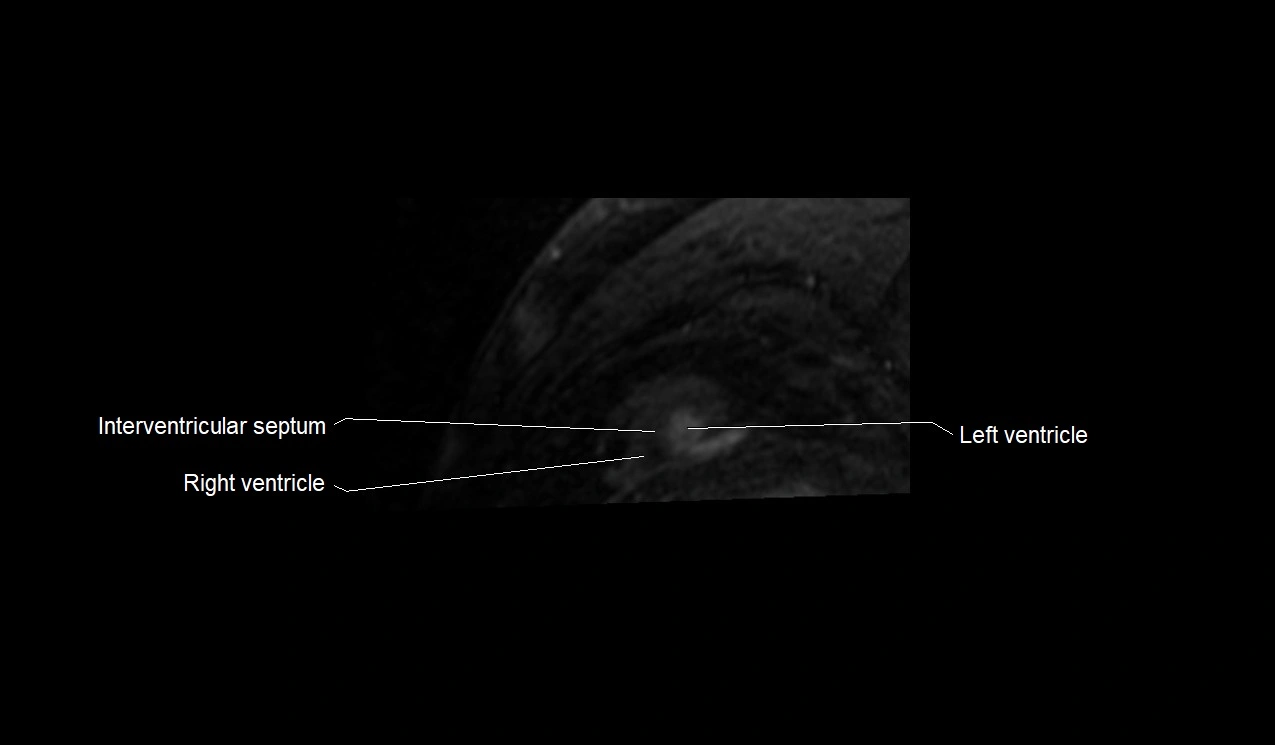

- Interventricular Septum

- Right ventricle

- Left ventricle